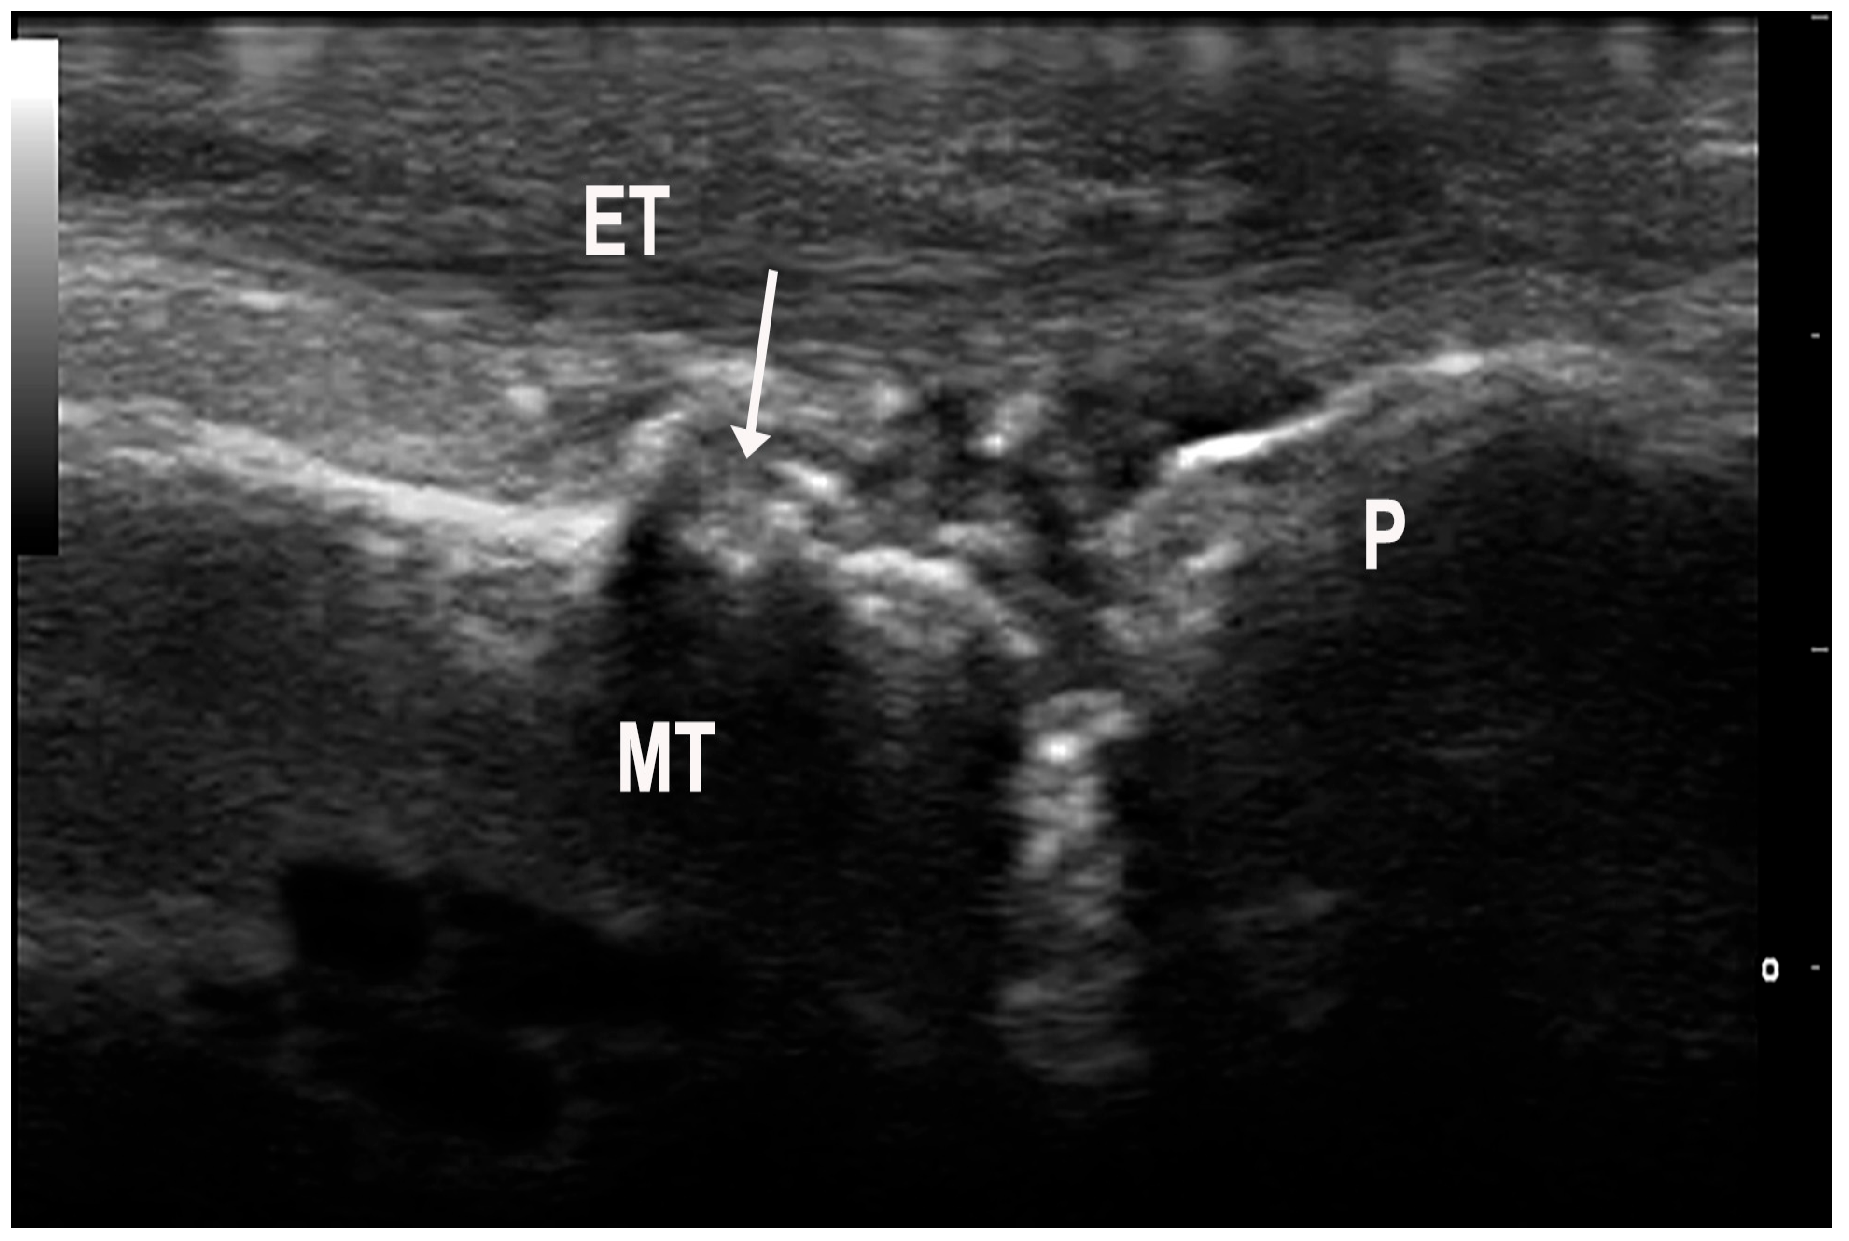

Figure 5.

Erosions (arrow) of the metatarsal head (MT) in a patient with gout. To note a grade 2 urate aggregate at the level of the metatarsophalangeal joint. ET—extensor tendon, P—phalanx.